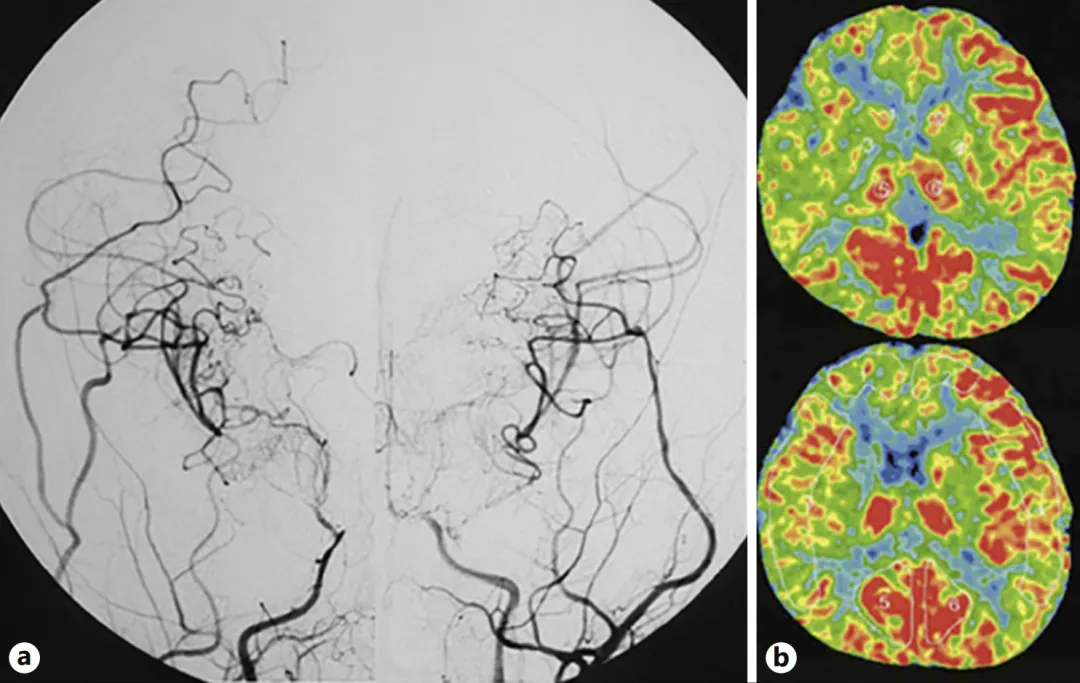

小患者术后恢复良好,复查DSA显示侧支循环建立良好,基底节区烟雾血管减少,脑血流显著改善。但术后还是需要继续用药预防血栓并同时严格控制血压。

图a:第二次手术半年后,双侧颈内动脉血管造影显示侧支血管网络发育良好,基底烟雾血管消退。

图b:双侧脑血流显示有所改善。